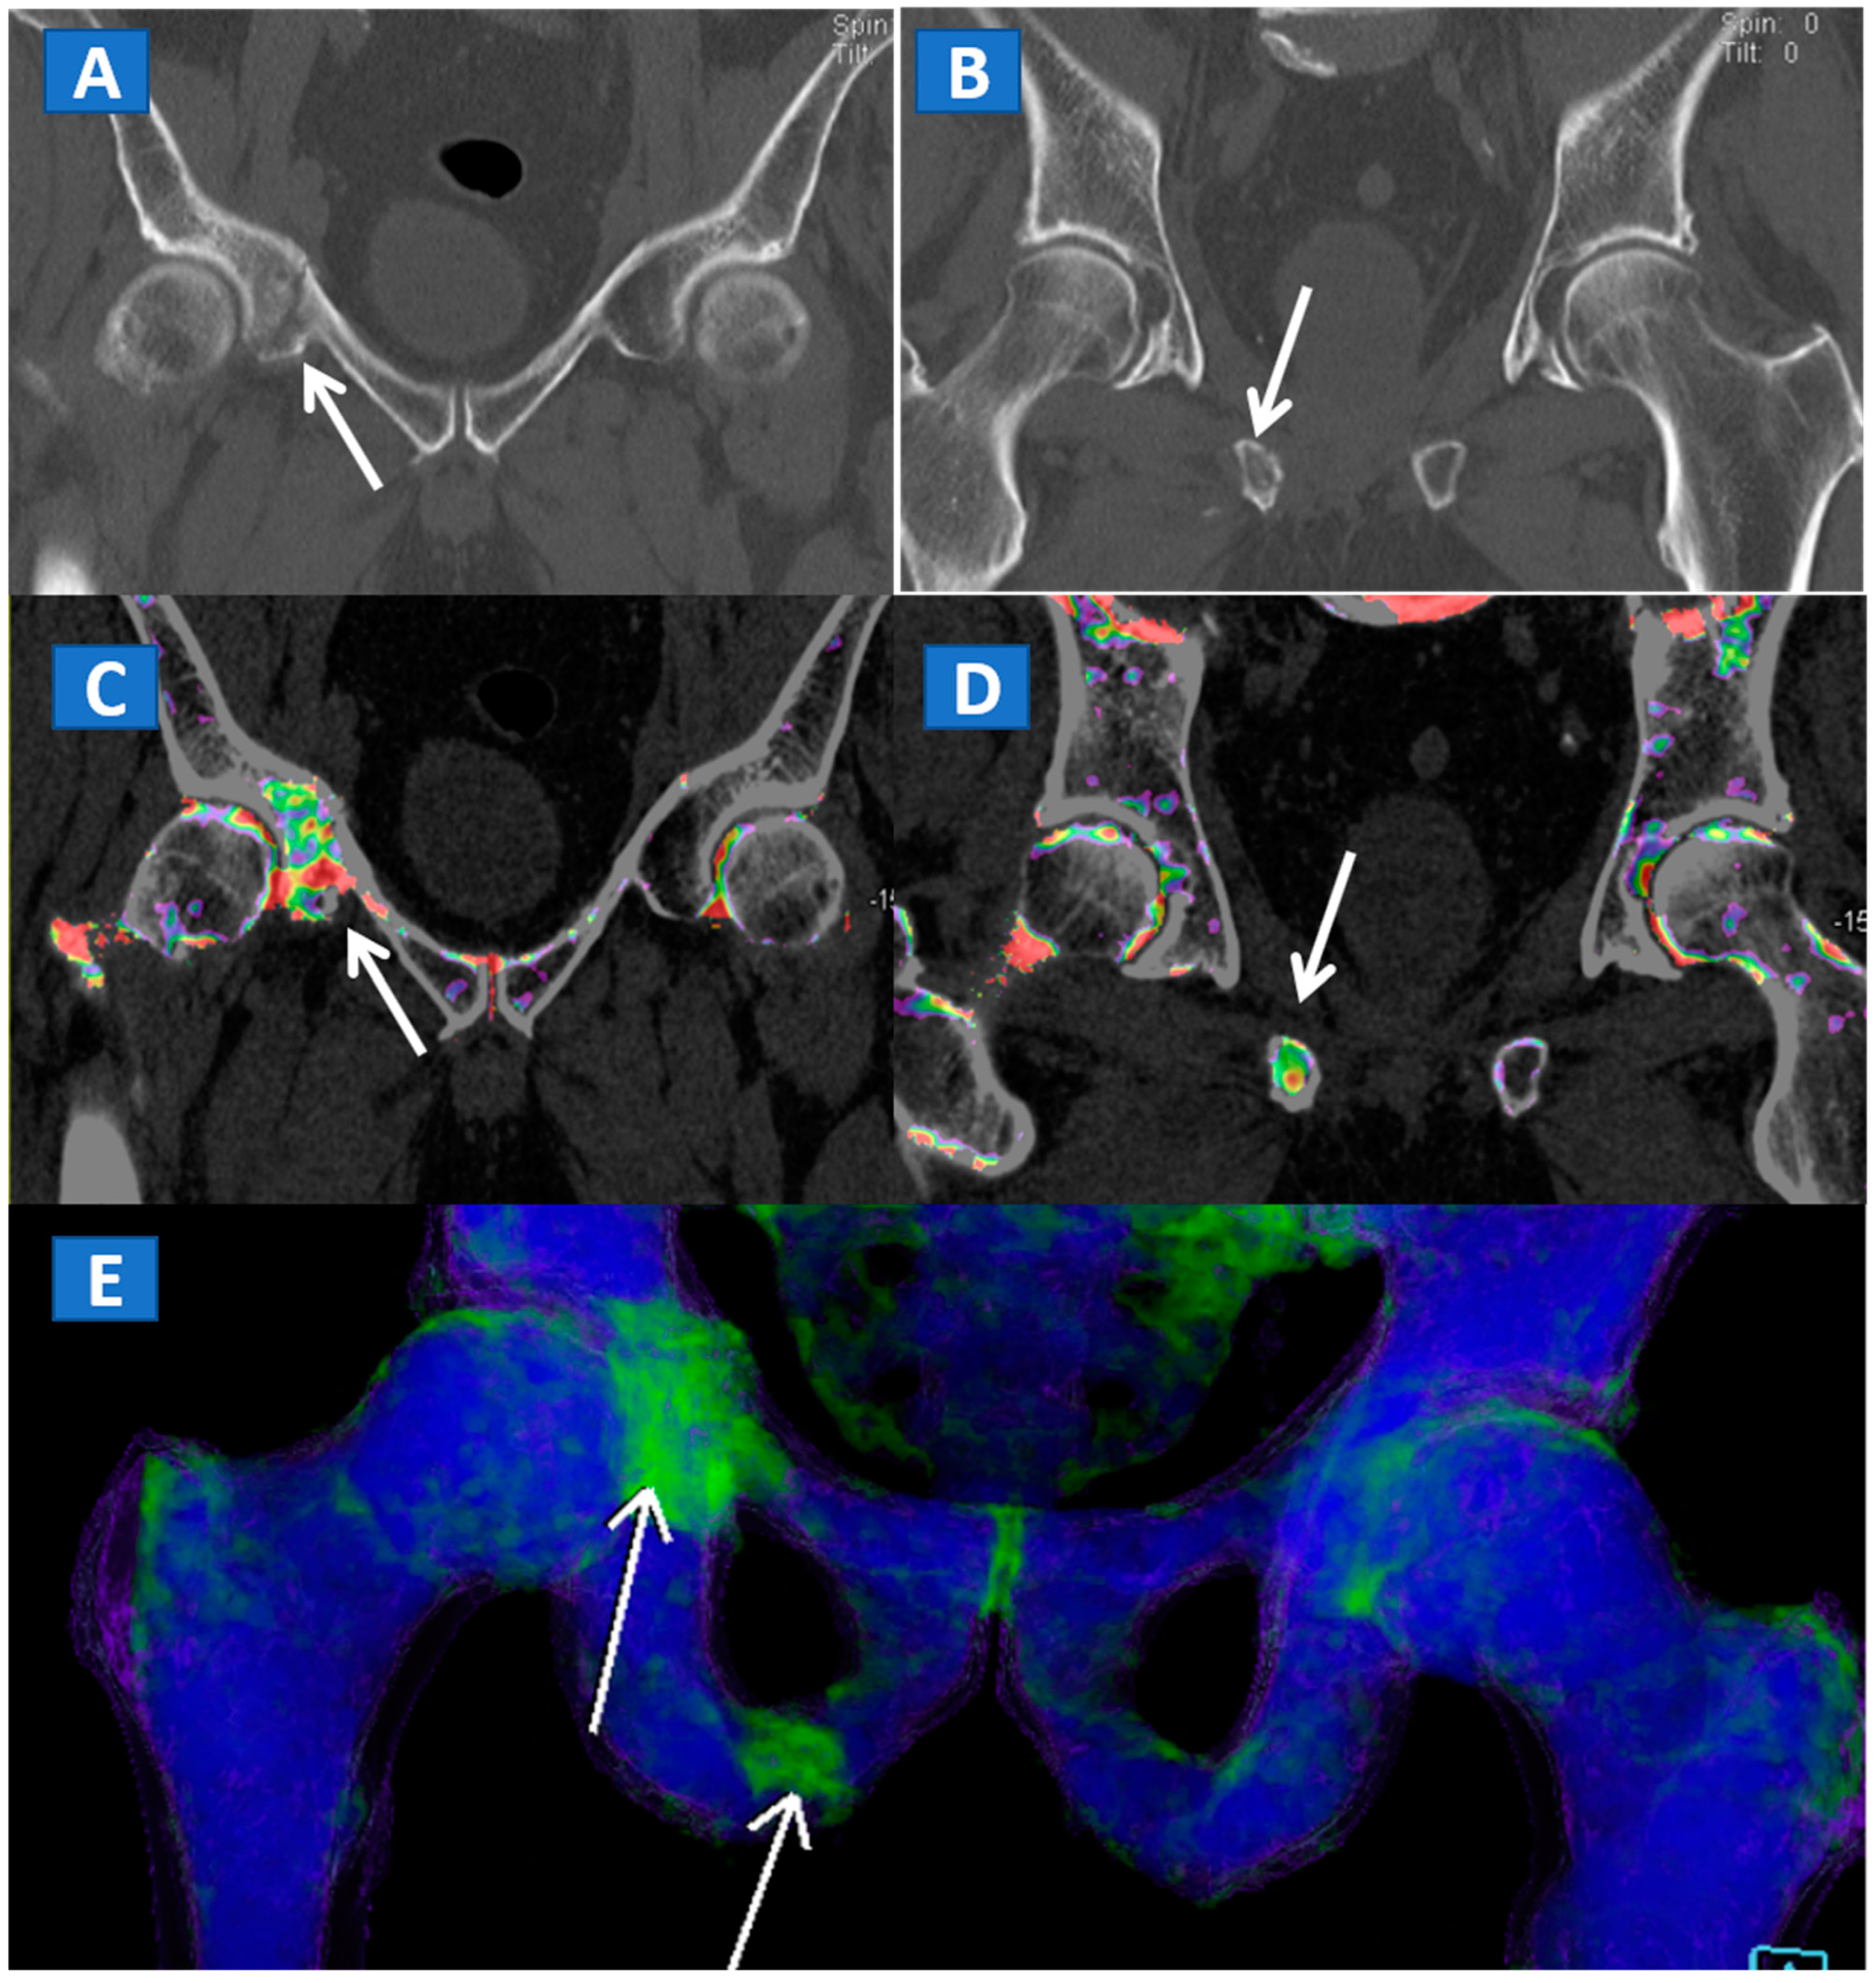

DECT can also accurately depict BME in traumatic hip injuries [2]. When evaluating pelvic bones, multiple non-displaced but clinically relevant fractures frequently arise in clinical practice, for instance, untreated cervical hip fractures, which risk future displacement (Figure 3). In such cases, DECT can increase the diagnostic accuracy and reduce the reading time, allowing the radiologist to identify and focus on oedematous areas, which usually correspond to the facture line. DECT also helps in depicting multiple fractures (Figure 4), avoiding the risk of satisfaction of search errors.

Figure 4.

A 61-year-old female with non-displaced fractures of the right iliac and pubic bones. On the standard coronal 1 mm CT images (A,B) the iliac fracture is well depicted (arrow in (A)), whereas the pubic fractures could be easily missed (arrow in (B)). The presence of BME on the corresponding 1 mm coronal reconstructed DECT images (C,D) confirms the non-displaced fractures. The 3D coronal DECT map (E) yields a clear picture, depicting the fractures of the right side and ruling out the presence of BME on the left side.